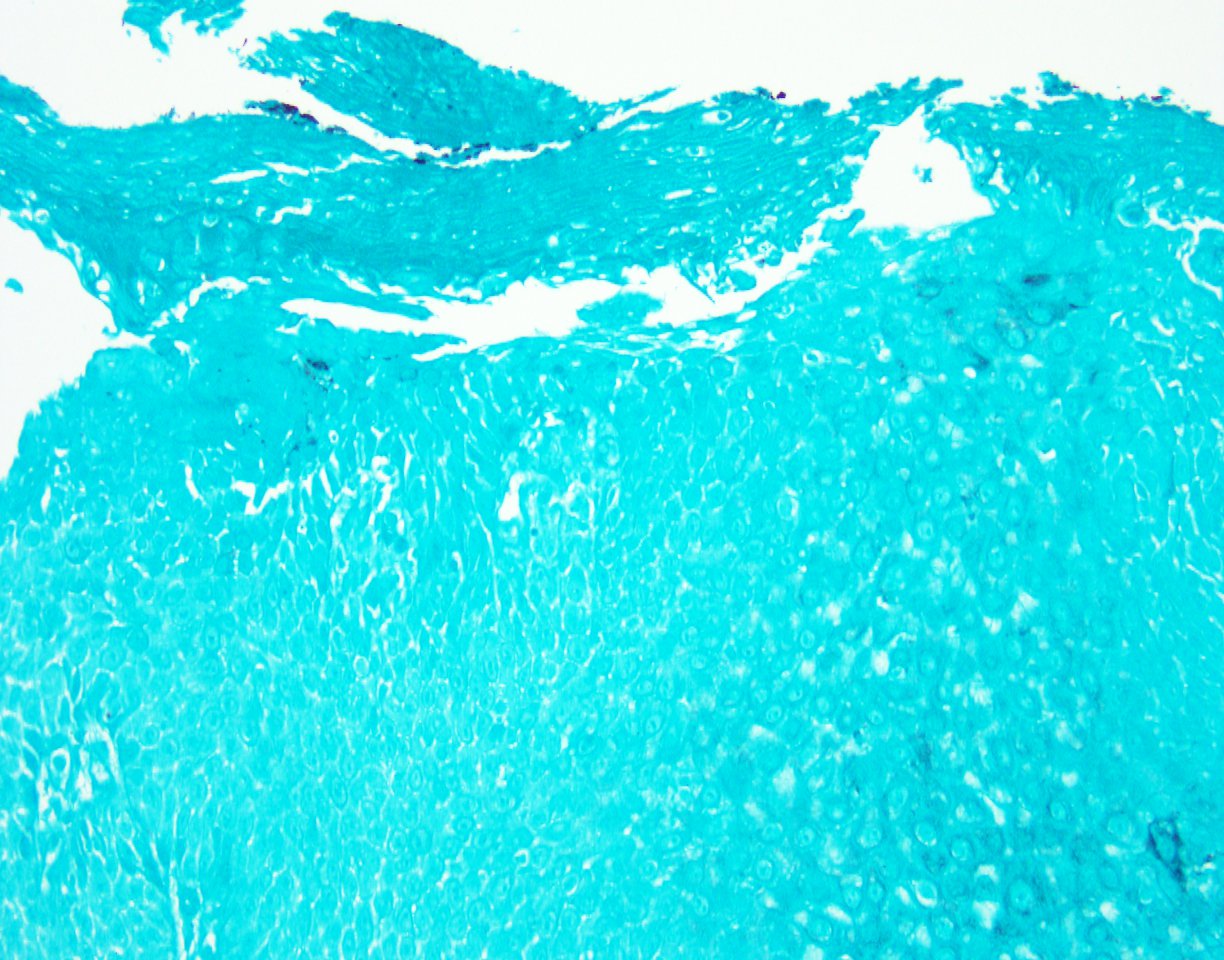

Histologically, the esophageal mucosa demonstrates hypertrophied squamous epithelium with a superficial zone of eosinophilic epithelium (Figures 1, 2). The superficial epithelium exhibits necrosis with faded or ‘ghost-like’ nuclei (Figure 2). A band of neutrophilic inflammation can be seen in some areas separating the two epithelial layers (Figure 3). Some of the tissue fragments in this biopsy specimen consist solely of the superficial necrotic material and neutrophilic junctional layer (Figure 4). GMS stain is negative for fungal organisms (Figure 5).